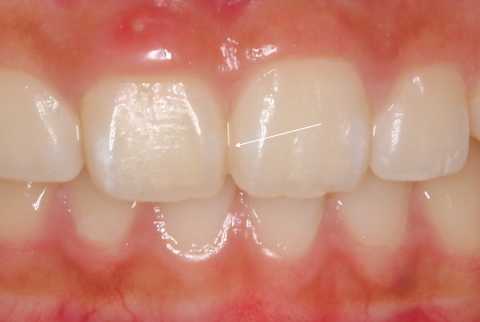

上顎のBefore/after

前歯の虫歯のBefore/after はこれだが、虫歯と言っても極表層だけで、そこにFeSが付着しているだけだと思う。飲食後の重曹うがいだけで維持管理できるのではないか?と思われる。

黒いFeSは歯を守ってくれていると考えるべきで、除去すると虫歯が進行する可能性が高い。